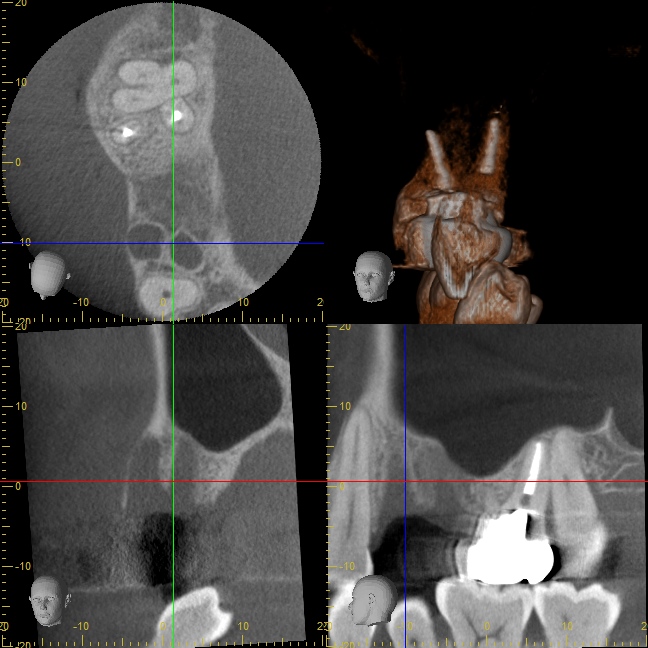

初診時のCT写真

残せない歯を他院さんで抜いたばかりのため、骨がとても少ない状態です。

こちらも顎骨が非常に薄く、上顎洞(副鼻腔)までの距離は3ミリくらいしかありません。